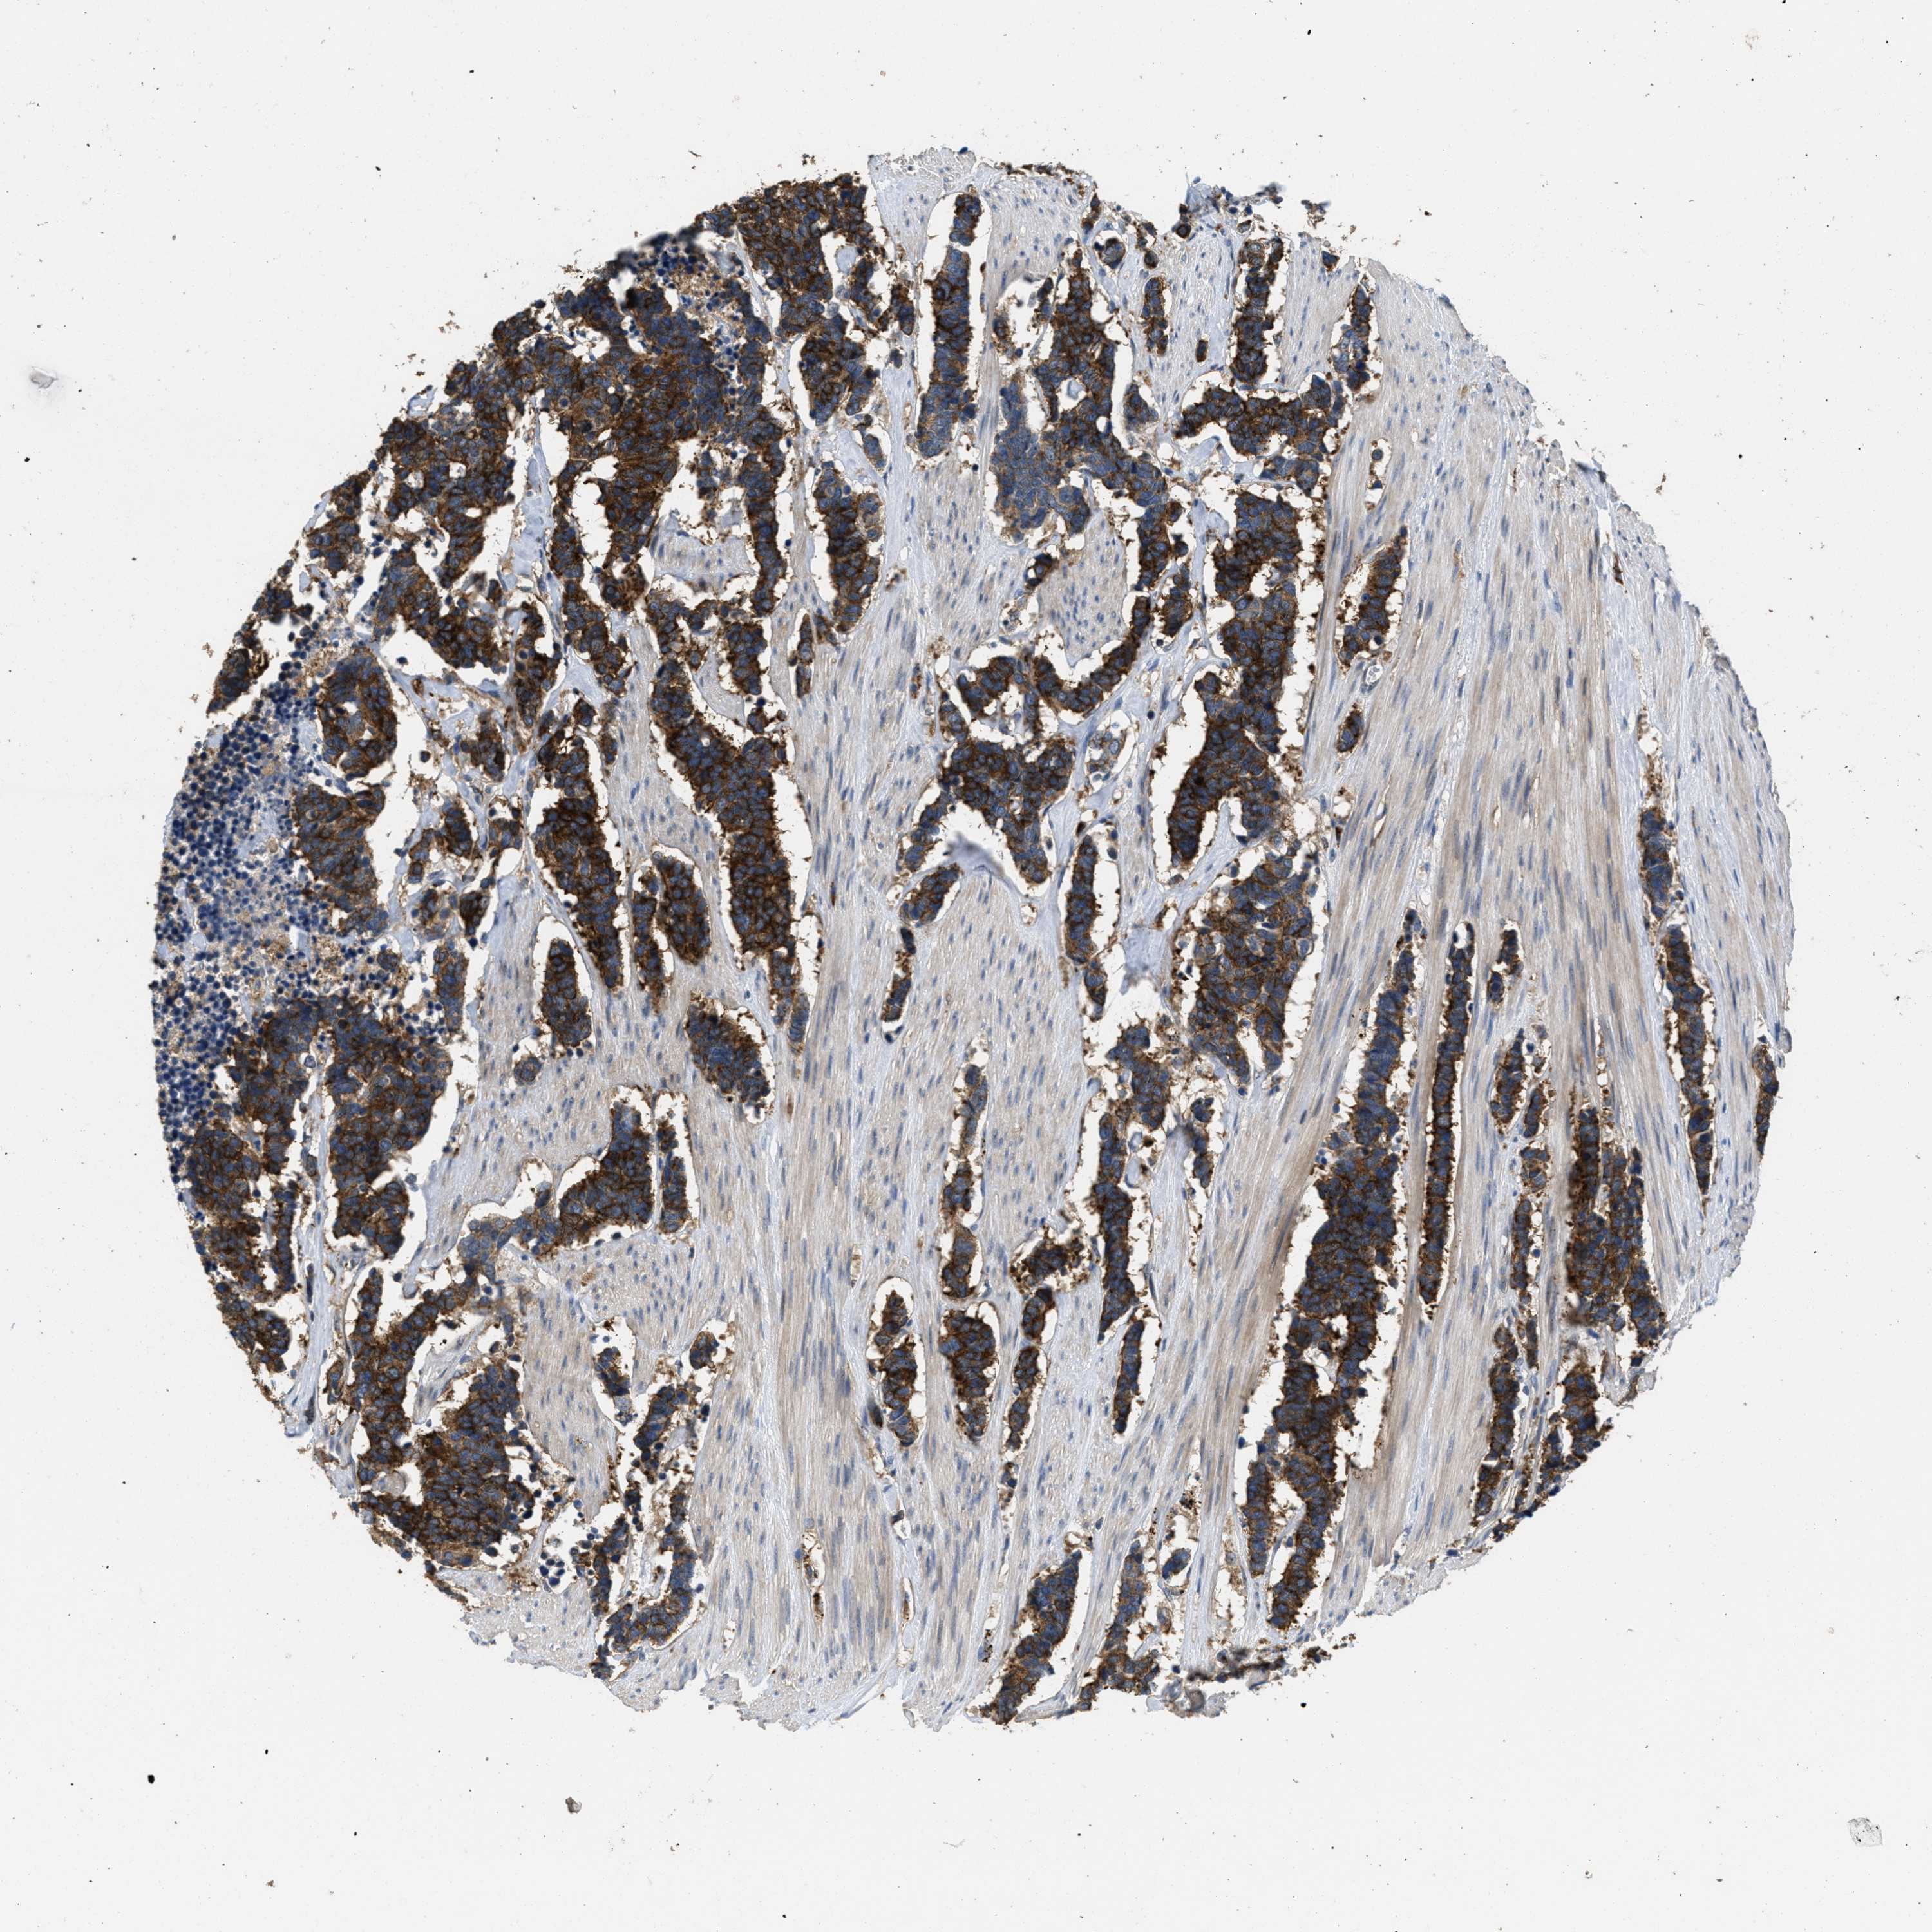

CARCINOID - Protein expressioni

A mouse-over function shows sample information and annotation data. Click on an image to view it in a full screen mode. Samples can be filtered based on level of antibody staining by selecting one or several of the following categories: high, medium, low and not detected. The assay and annotation is described here.

Each image is clickable and will lead to virtual microscopy that enables deeper exploration of all samples and also displays staining intensity scores, fraction scores and subcellular localization as well as patient and tissue information for each sample.

Antibody HPA017278

Intensity

Strong

Moderate

Weak

Negative

Quantity

>75%

75%-25%

<25%

None

Location

Nuclear

Cytoplasmic/membranous

Cytoplasmic/membranous,nuclear

Carcinoid, malignant, NOS

Carcinoma, NOS